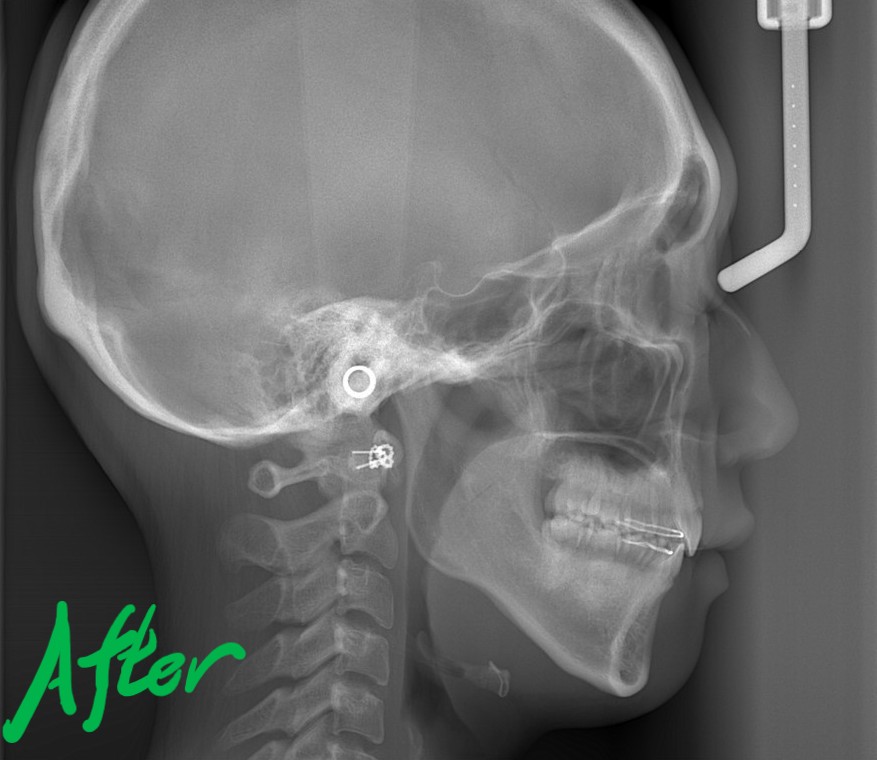

次に、レントゲン写真の比較です。

左側が矯正治療前、右側が矯正治療後

矯正後の状態をレントゲン写真で確認すると、